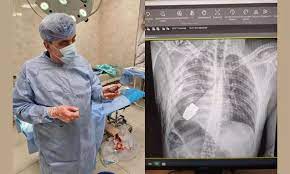

அதேசமயம் உடனடியாக அறுவை சிகிச்சை செய்து குண்டை அகற்றாமல் விட்டால், குண்டு வெடித்து, அந்த வீரர் உடல்சிதறி இறக்கும் அபாயம் நிலவியது. இந்த நிலையில் உக்ரைன் ராணுவத்தில் பணியாற்றும் மிகவும் அனுபவம் வாய்ந்த அறுவை சிகிச்சை நிபுணர்களில் ஒருவரான டாக்டர் ஆண்ட்ரி வெர்பா மிகவும் துணிச்சலுடன் அந்த ராணுவ வீரருக்கு அறுவை சிகிச்சை செய்ய முன்வந்தார்.

அவரது பாதுகாப்புக்காக வெடிகுண்டு நிபுணர்கள் 2 பேர் அறுவை சிகிச்சை நடந்த அறையில் நிறுத்தப்பட்டிருந்தனர். மின்சார கருவிகளை பயன்படுத்தி அறுவை சிகிச்சை செய்தால் கையெறி குண்டு வெடிக்க வாய்ப்பு உள்ளது என்பதால் டாக்டர் ஆண்ட்ரி வெர்பா அவற்றை பயன்படுத்தாமல் வெற்றிகரமாக அறுவை சிகிச்சை செய்து ராணுவ வீரரின் மார்பில் இருந்து கையெறி குண்டை அகற்றினார்.

இதையடுத்து அங்கு தயாராக இருந்த வெடிகுண்டு நிபுணர்கள் அதை செயலிழக்க செய்தனர். அறுவை சிகிச்சைக்கு பின் ராணுவ வீரர் நலமாக இருப்பதாக அங்கிருந்து வரும் தகவல்கள் தெரிவிக்கின்றன. ஆபத்தான சூழலில் துணிச்சலாக உயிரை பணயம் வைத்து ராணுவ வீரரை காப்பாற்றிய உக்ரைன் டாக்டரை பலரும் பாராட்டி வருகின்றனர்.